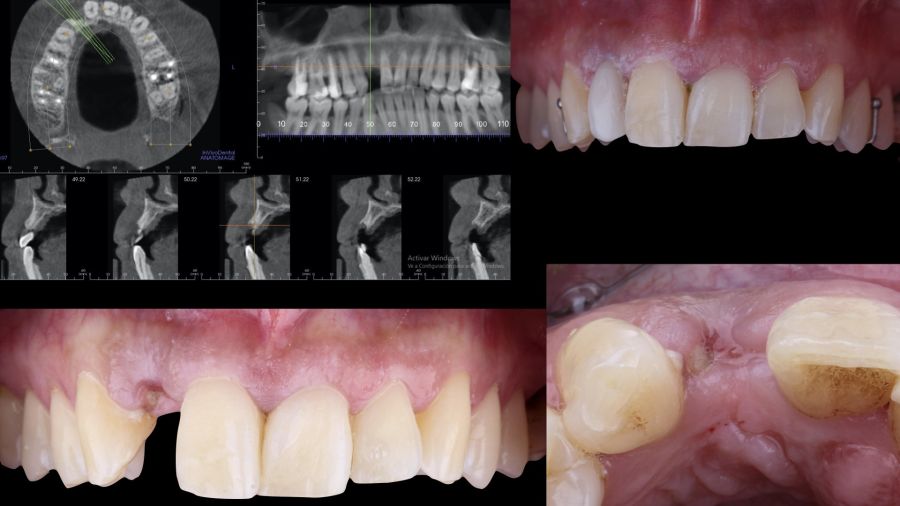

Una mujer de 29 años acudió a nuestra clínica dental tras sufrir un traumatismo en el incisivo lateral superior derecho (1.2). Tras el traumatismo, el diente sufrió una fractura de toda la corona anatómica, por lo tanto, solo presentaba un resto radicular en posición subgingival. El resto radicular se diagnosticó como no restaurable por lo que se valoraron detenidamente las opciones terapéuticas disponibles con la paciente. Se decidió reemplazar el diente 1.2 con un implante dental y se elaboró el siguiente plan de tratamiento y secuencia clínica; Fase I: extracción del resto radicular 1.2 y reconstrucción del proceso alveolar utilizando un procedimiento de preservación alveolar no invasivo. Restauración provisional inmediata mediante una prótesis parcial de acrílico removible. Fase II: colocación guiada de un implante y aumento de espesor mucoso mediante un injerto de tejido conectivo. Fase III: conformación y modelado del perfil de emergencia mediante una prótesis provisional directa a implante y restauración cerámica sobre implante definitiva.

-Fase II: la cicatrización transcurrió sin complicaciones. Tras 5 meses de la cirugía de preservación alveolar, se planificó la cirugía implantológica guiada en posición 1.2 (Figura 2). Para ello, se utilizaron un archivo DICOM procedente de la tomografía computarizada de haz cónico (CBCT) y el archivo STL procedente del escaneado mediante un escáner óptico intraoral. Con esta información se construyó una férula quirúrgica de soporte dental (Figura 3). La férula quirúrgica se ancló sobre los dientes y guió la realización del lecho implantario y la colocación del implante. La técnica quirúrgica de cirugía guiada consistió en una cirugía con colgajo, preparando e insertando el implante (3,5 x 11,5 mm) según el protocolo estandarizado de cirugía guiada Nobel Active® (Nobel Biocare AB, Gothenburg, Sweden). Una vez colocado el implante 1.2, se obtuvo un injerto gingival compuesto de epitelio y tejido conectivo de la mucosa masticatoria palatina. A continuación, se realizó la desepitelización de la capa superficial de dicho injerto fuera de boca mediante una hoja de bisturí 15C con la finalidad de obtener un injerto de tejido conectivo de la capa subyacente18.

-Fase III: tres meses tras la colocación del implante, la situación del tejido blando era favorable (Figuras 5 y 6). Se tomó una impresión digital mediante escáner intraoral para la realización de un provisional atornillado de polimetilmetacrilato (PMMA). Respecto a la corona implantaria definitiva se realizó una restauración cemento-atornillada con una interfase de titanio nitrurado adaptando el diseño al perfil de emergencia ya consolidado con la prótesis provisional. La corona se realizó por CAD-CAM en zirconio con reducción completa y estratificación de cerámica feldespática de recubrimiento para zirconio (Figura 7).